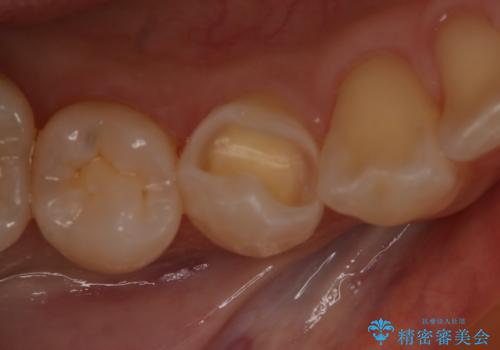

- 右下4番の虫歯治療を希望され来院された患者様です。

セラミックでの治療を希望されたため、切削量・形態を考慮しセラミックインレーでの治療を計画しました。

う蝕を除去した後、CRで裏層した上で形成、印象をしています。

装着時にはラバーダムを使用しています。